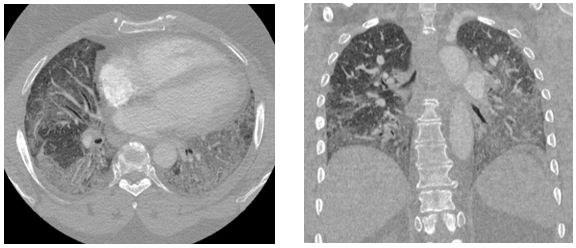

Representative images from her chest CT scan are shown below. Bronchoscopy with transbronchial biopsy and microbiological analysis were negative for evidence of infection, malignancy, and granulomatous disease.